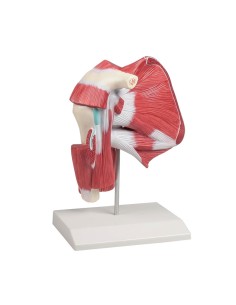

Dal cranio in 22 parti con incastri magnetici ai modelli di colonna vertebrale, da quelli di articolazioni a quelli di cuore, ogni pezzo della nostra collezione è progettato per un’immersione totale nello studio dell’anatomia umana. I nostri modelli, realizzati tramite scansioni di ossa vere, garantiscono un’esperienza tattile autentica e una fedeltà di peso quasi identica agli originali.

Essenziali per studenti e professionisti, i nostri modelli anatomici sono strumenti didattici che permettono di osservare le strutture anatomiche con precisione, eliminando la necessità di dissezioni o studi invasivi. Sono inoltre utili per spiegare ai pazienti le patologie, rendendo la comunicazione più efficace e risparmiando tempo prezioso.